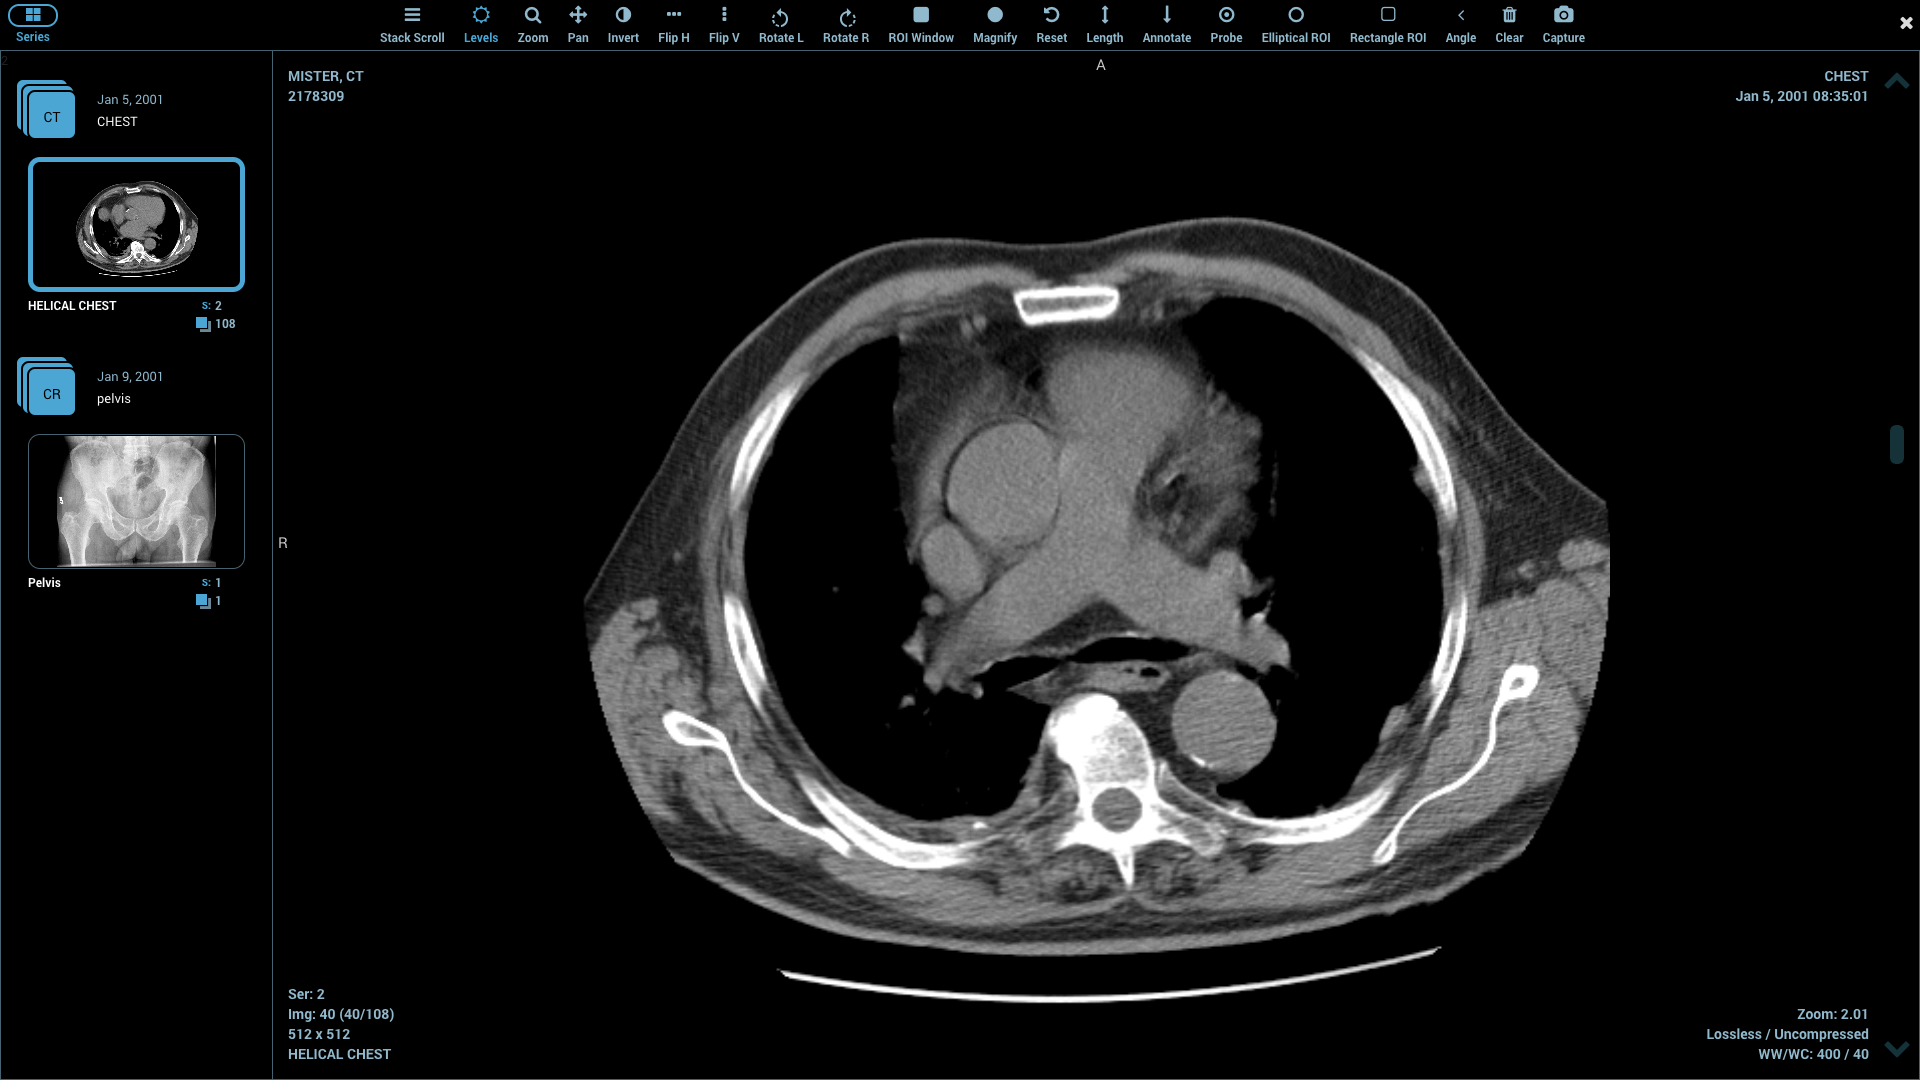

Most DICOM applications today read common imaging modalities like CT, MRI, and ultrasound images. Features such as multiplanar reconstruction (MPR), particularly 3D reconstruction, are needed for treatment planning. Volume rendering, maximum and minimum intensity projections (MIPs) aid in diagnosis as well as in research. Image fusion, such as PET to CTs or PET to MRIs can also help in diagnosis and reporting.

Keeping the above purposes in mind, and allowing for ease of use and installation by end users themselves, we have compiled the following list that includes the most convenient, useful, and affordable DICOM viewers out there: